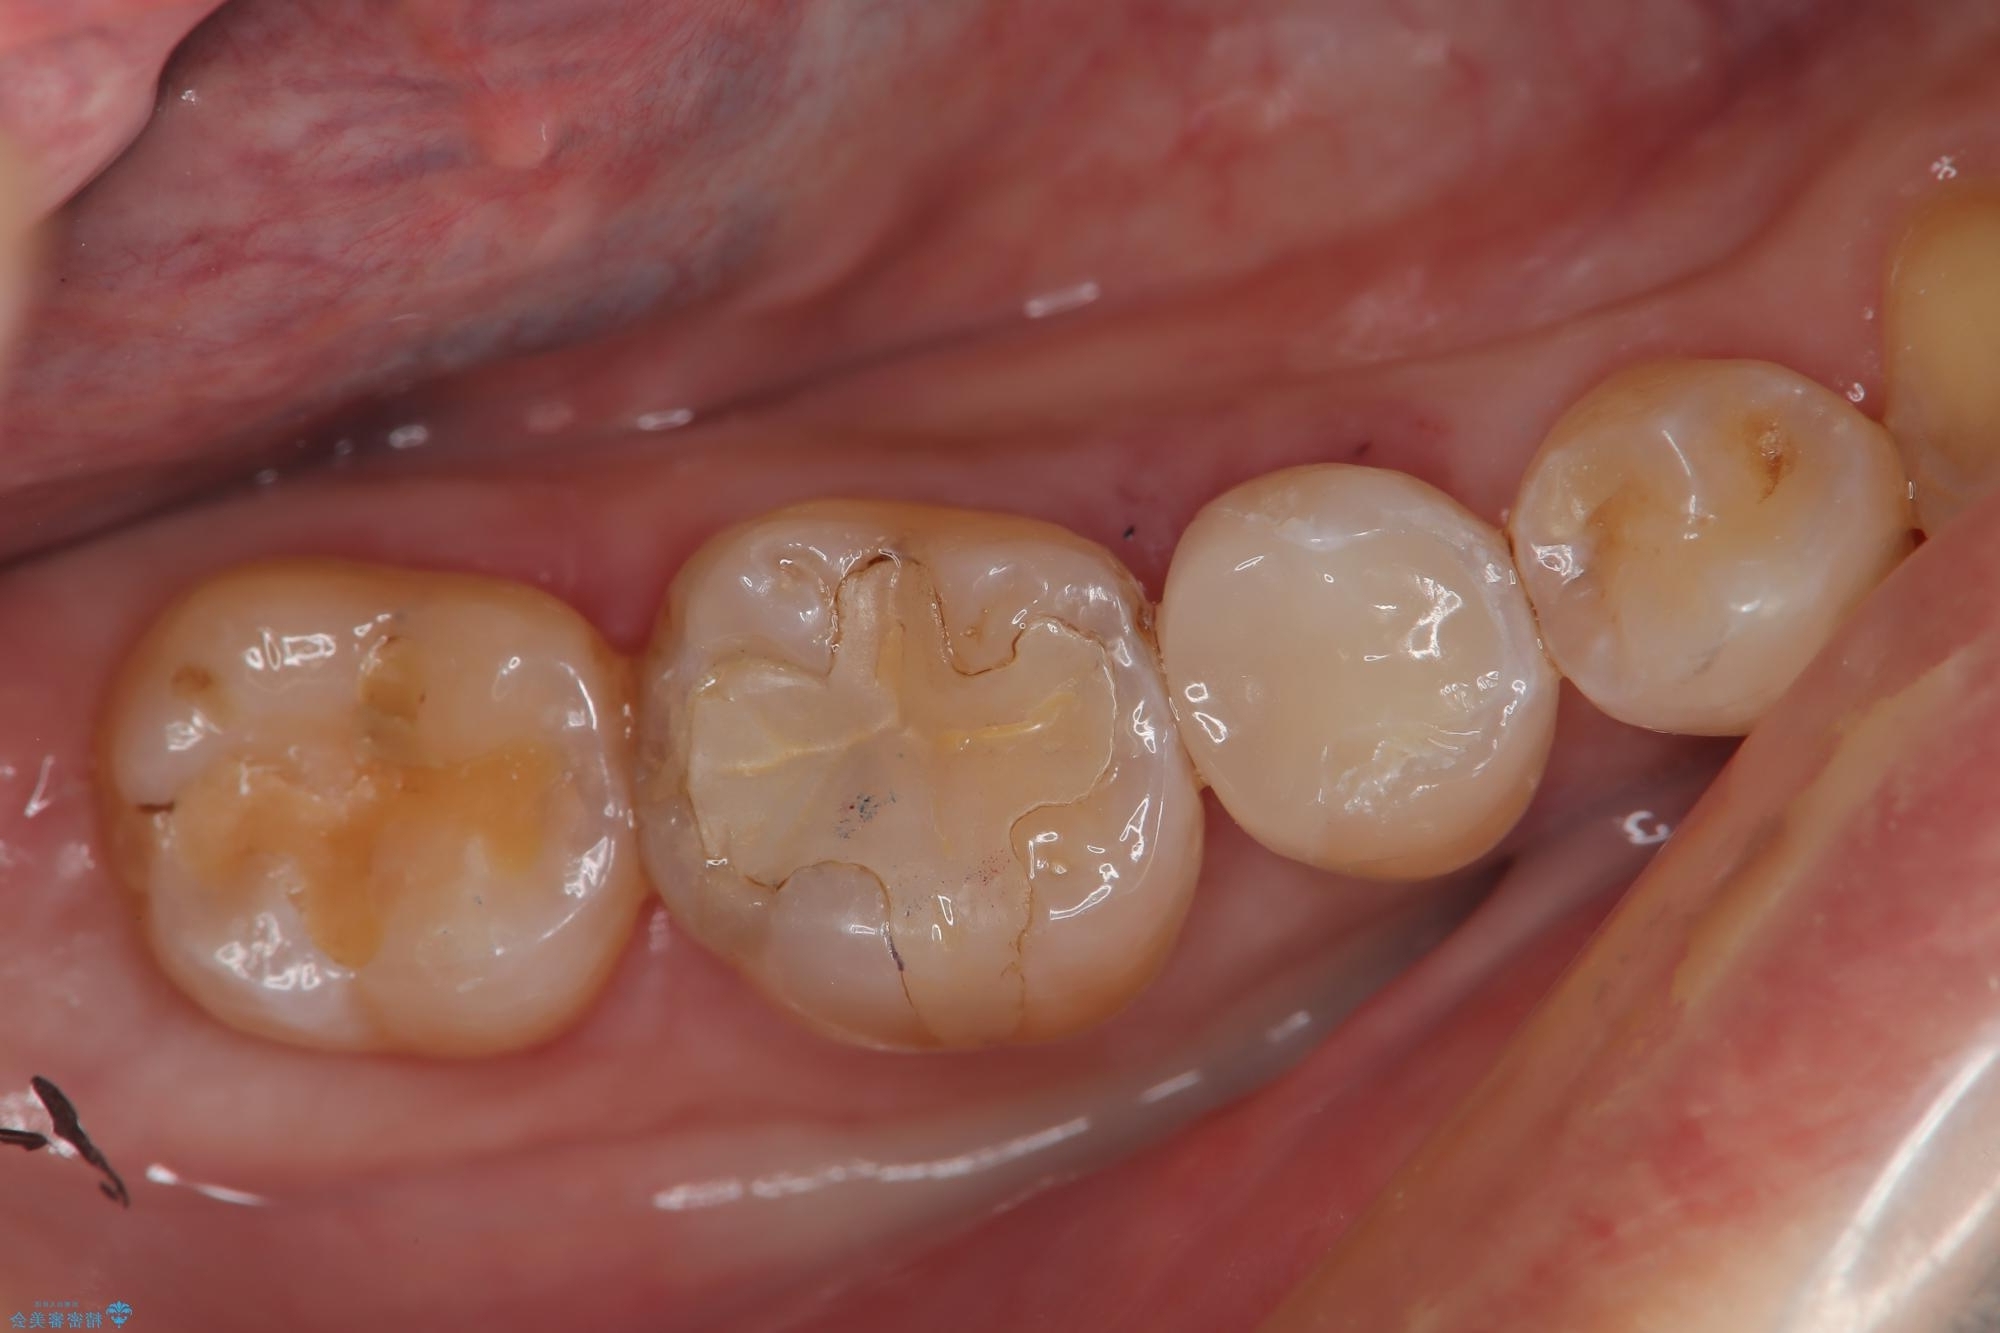

レントゲン検査の結果、古い金属の詰め物の内部に二次的な虫歯が見つかりました。

この虫歯を完全に除去した後、その日のうちに精密なセラミックインレーに替える治療を行いました。術後の経過も良好です。